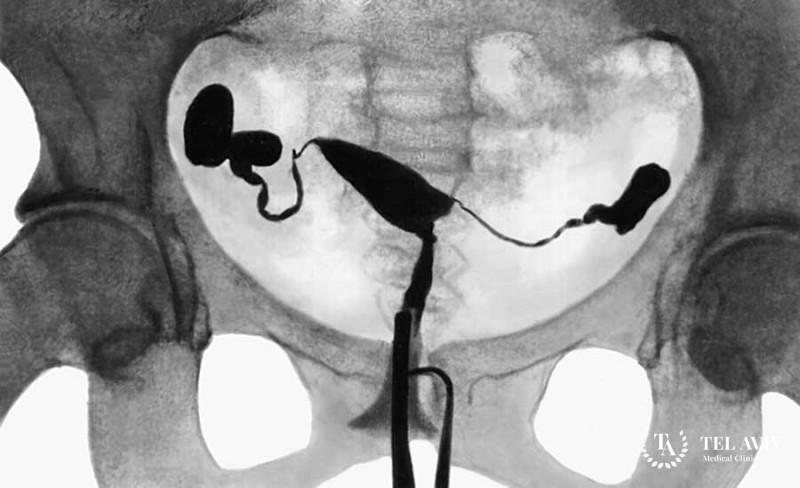

Неправильное функционирование маточных труб способно стать препятствием к зачатию ребенка. Понять, что конкретно мешает их проходимости можно с помощью такого метода рентгенодиагностики, как гистеросальпингография. Проводить процедуру разрешается только под контролем врача, который введет во влагалище пациентки контрастные препараты. После попадания в полость матки вещества, женщину укладывают таким образом, чтобы лучи аппарата охватывали нужный участок тела.

Препарата требуется столько, чтобы получилось достаточное количество информативных снимков. Женщина может испытывать некоторый дискомфорт и даже болезненные ощущения, поэтому допускается применение премедикации, чтобы снять спазмы. Время проведения составляет около 40 минут, после чего пациентке следует еще полежать, чтобы избежать кровотечения.